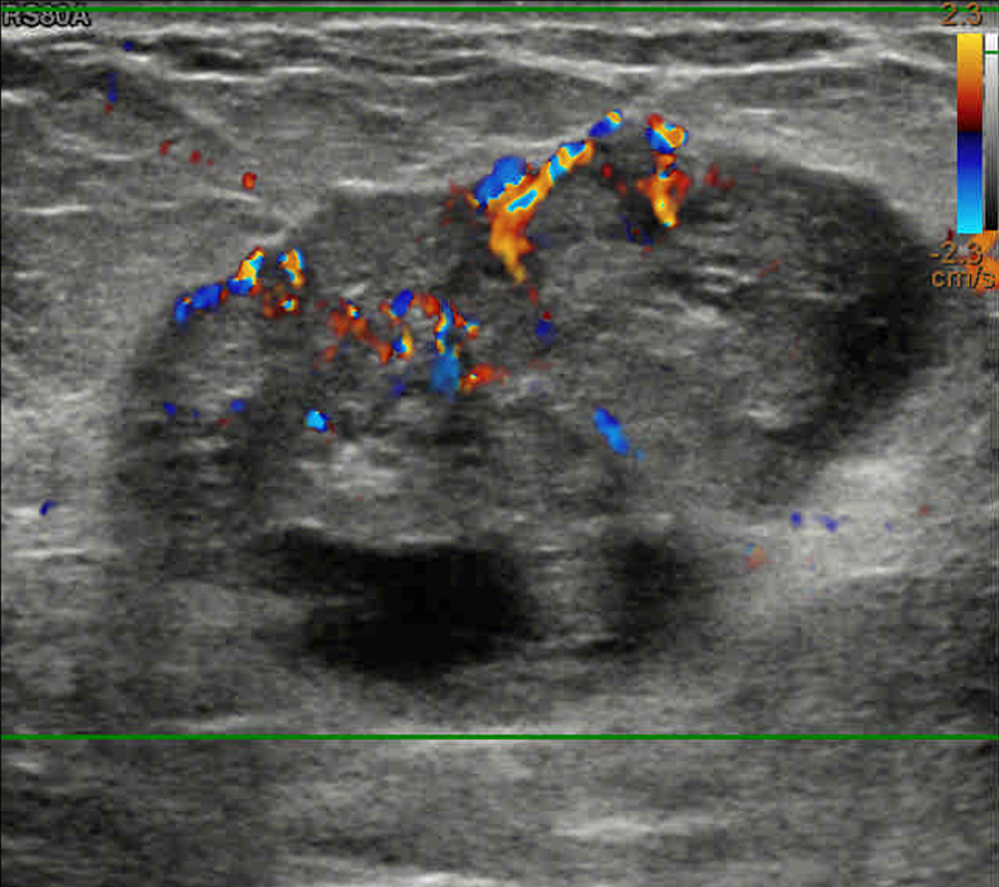

Malignant Solid Mass

Doppler

Case-167-D1